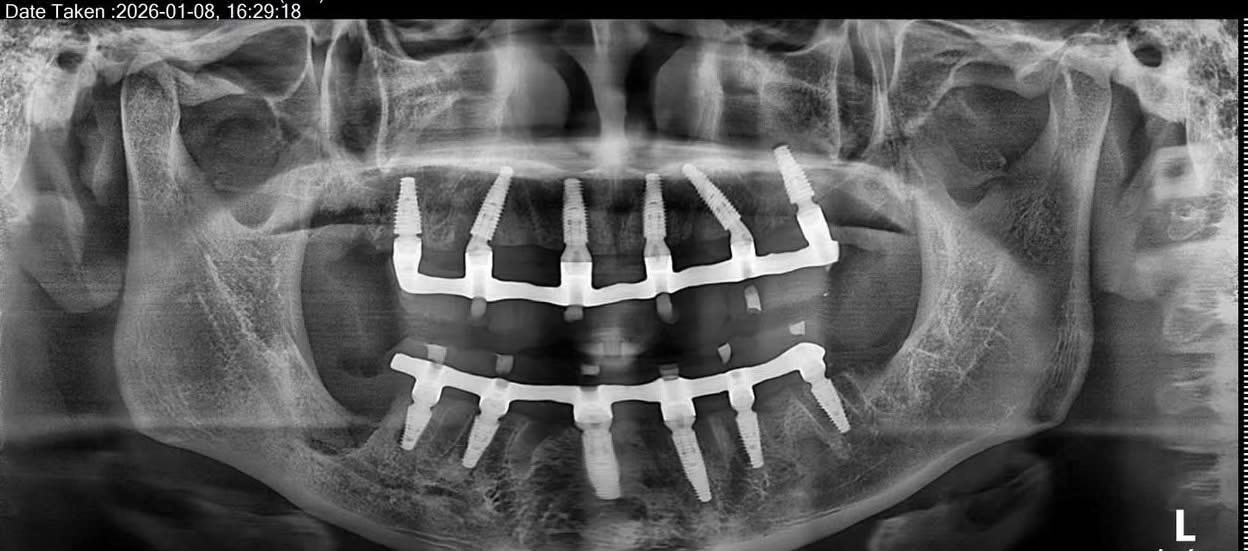

Cấy ghép Implant toàn hàm và phục hình tức thì sau 24h tại Nha Khoa Như Ngọc (21 Trần quang diệu, Hà Nội)